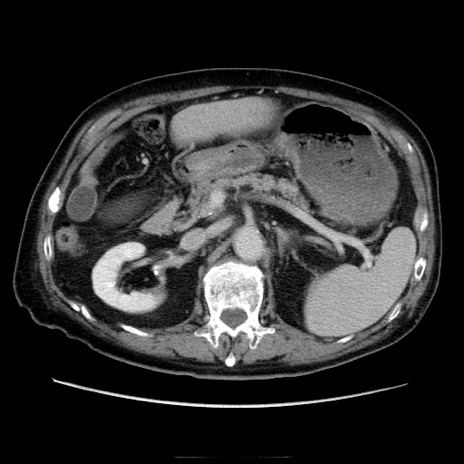

症例21(横断像)

冠状断像

【症例】70歳代男性

【主訴】腹痛

【現病歴】肝硬変・肝細胞癌にてかかりつけの方。約9時間前に食後より腹痛出現。症状が徐々に増悪し、嘔吐出現したため来院。

【既往歴】肝硬変、肝細胞癌(RFA、TACE後)

【身体所見】意識清明、表情苦悶様、BT 36℃、BP 129/78mmHg、P 88bpm、SpO2 97%(RA)、右上腹部から心窩部にかけて圧痛あり、反跳痛なし、筋性防御あり。

【データ】WBC 5800、CRP 0.16